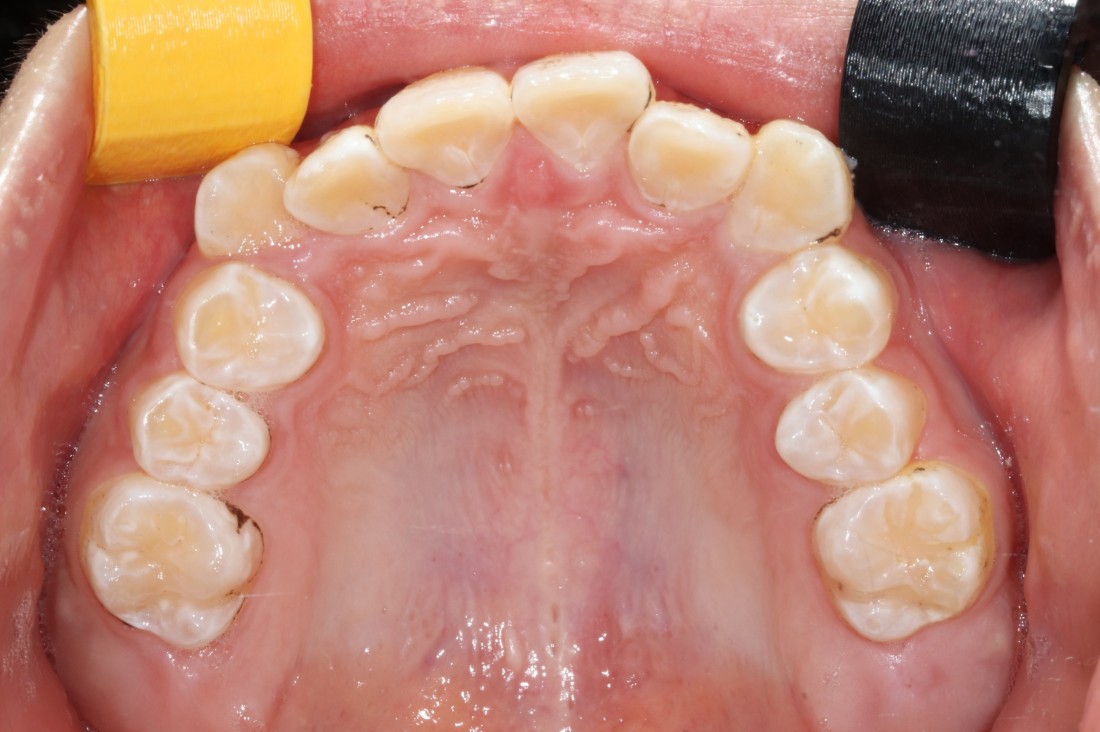

광산구 교정치과는

대표원장 5인 협진 시스템으로

운영하고 있습니다.

발치교정이 필요할 때 발치부터

충치치료, 필요한 경우 임플란트 진료까지

각 분과별 전문의 대표원장이

각각 본인의 파트를 맡아서

최상의 치료계획을 세우고 있습니다.